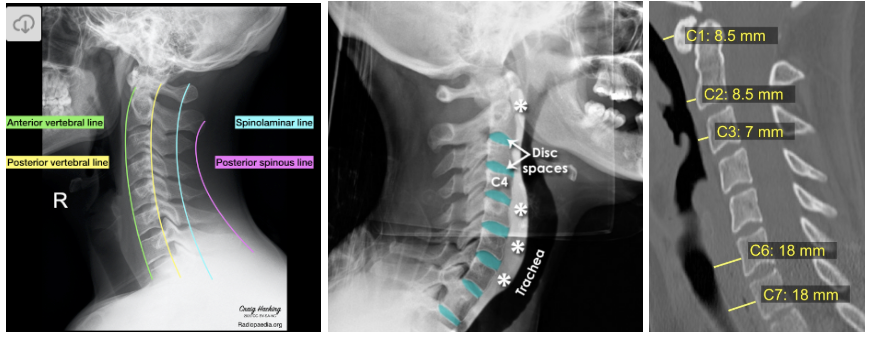

Once you determine if a patient needs a CT imaging of their neck and obtain the scans, make sure to get into the habit of reading them on your own. While reading CT scans of the c-spine can appear overwhelming, this process can be easily done if you follow these simple “ABC’S”:

A - Alignment - trace along the anterior vertebral line (anterior longitudinal ligament), posterior vertebral line (posterior longitudinal ligament), spinolaminar line (ligamentum flavum), and tip of the spinous processes to see of for any disruptions

B - Bones - assess the bones in the axial/sagittal/coronal views for any fractures

C - Cartilage - evaluate for any narrowing or asymmetry between the vertebral bodies and spinous processes

S - Soft tissue - examine the prevertebral soft tissue (narrower 5-10mm from C1-C4 and thickens starting C5 due to esophagus lying anteriorly) since soft tissue swelling my point towards a fracture